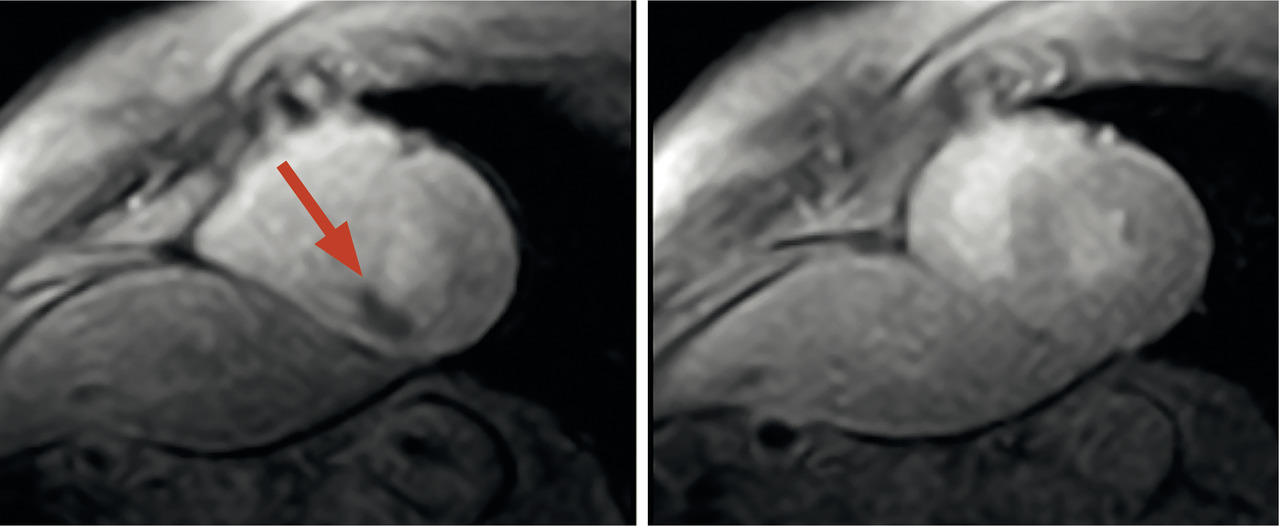

IRM de stress

L’agent « stresseur », vasodilatateur (adénosine ou dipyridamole), multiplie par 4 à 5 le débit coronaire versus l’état basal.

Une sténose coronaire est dépistée par la majoration significative du gradient de pression de part et d’autre de son rétrécissement. Les séquences dynamiques après injection d’un produit de contraste de type gadolinium sont réalisées au pic de stress pharmacologique. Sa diffusion sanguine rehausse successivement les cavités cardiaques droites puis gauches, puis le muscle cardiaque (de l’épicarde vers l’endocarde) formant une image homogène du myocarde s’il est sain.

Un défaut de perfusion se voit à une lacune du rehaussement myocardique sous forme d’hyposignal, et témoigne d’une ischémie coronaire.5 Dans certains centres, quand le test à l’adénosine est positif, on injecte de la dobutamine à la recherche d’un trouble de la contractilité dans la zone hypoperfusée, afin d’accroître la puissance diagnostique. Cette IRM à la dobutamine n’est pas de pratique courante, en raison de sa durée prolongée et de sa mauvaise tolérance clinique.